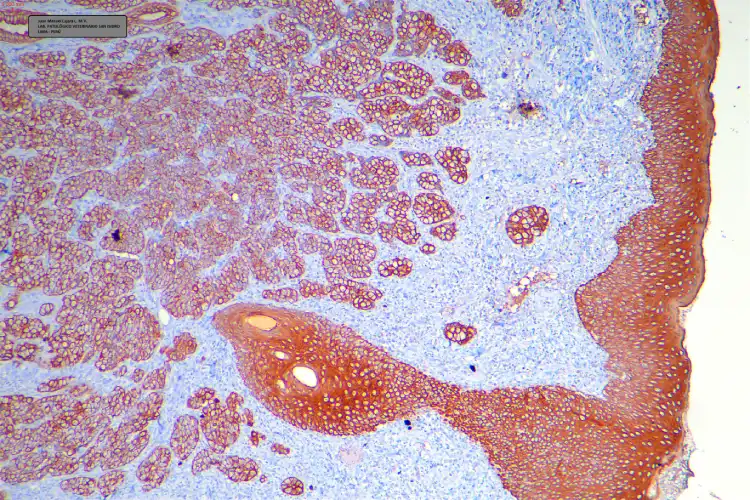

Los resultados fueron conversados con el equipo de la clínica y consultados con el oncólogo veterinario. Se decidió realizar estudios de INMUNOHISTOQUÍMICA confirmatorios para iniciar el tratamiento. Para la confirmación se optó por el marcador de Citoqueratina (CK) el cual brindó una reacción positiva intensa con las células tumorales del tejido (Foto C 1-2)

FOTO C-1

FOTO C-2